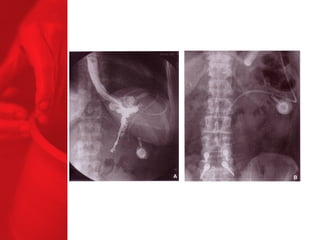

DIVERSION BILIO-PANCREATIQUE (DBP)AVEC «SWITCH DUODENAL» Procédure de malabsorption Poche de l'estomac plus grande Plus grande perte de poids Plus grande malabsorption des nutriments Perte de surcharge pondérale de 74% la première année, 78% la deuxième année, 81% la troisième année, 84% la quatrième année et 91% la cinquième année*. Diminue le diabète de type 2 chez près de 77% des patients** *Duodenal Switch: An Effective Therapy for Morbid Obesity – Intermediate Results” Baltasar A, Bou R. Obesity Surgery 2001 Feb; 11(1): 54-8. ** Buchwald H, Avidor Y, Braunwald E, et al. Bariatric Surgery—A Systematic Review of the Literature and Meta-analysis. Journal of the American Medical Association 2004 Oct 13;292(14).

DIVERSION BILIO-PANCREATIQUE (DBP) AVEC «SWITCH DUODENAL» Procédure de malabsorption Poche de l'estomac plus grande Plus grande perte de poids Plus grande malabsorption des nutriments Perte de surcharge pondérale de 74% la première année, 78% la deuxième année, 81% la troisième année, 84% la quatrième année et 91% la cinquième année*.   Diminue le diabète de type 2 chez près de 77% des patients** *Duodenal Switch: An Effective Therapy for Morbid Obesity – Intermediate Results” Baltasar A, Bou R. Obesity Surgery 2001 Feb; 11(1): 54-8. ** Buchwald H, Avidor Y, Braunwald E, et al. Bariatric Surgery—A Systematic Review of the Literature and Meta-analysis. Journal of the American Medical Association 2004 Oct 13;292(14).